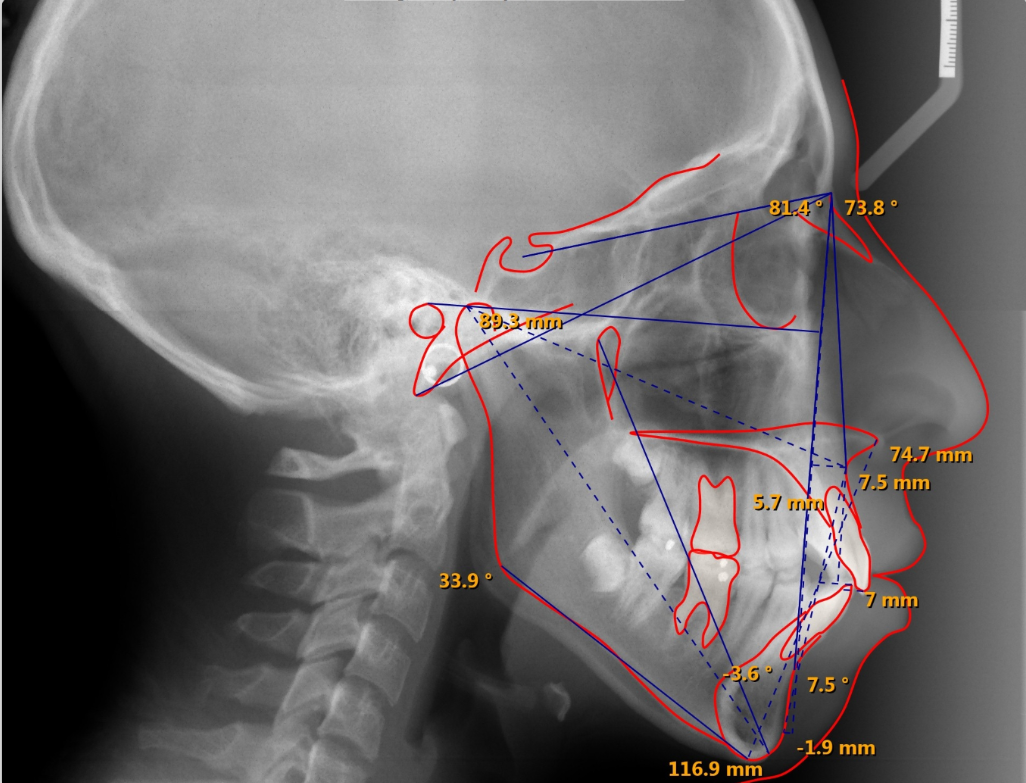

Ceph Tracing and Analysis

Ceph tracing makes your life simpler by automatically selecting and positioning each structure to be traced, then prompting you for final placement. With SmartCeph, you can superimpose multiple timepoints by plane or manually align them on the fly to meet your specific needs.